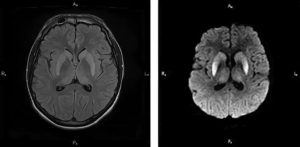

На PD/T2WI и FLAIR выглядит гиперинтенсивно. На PD/T2WI и FLAIR последовательностях возможно диагностировать до 80% инфарктов впервые 24 часа, но впервые 2-4 часа после инсульта изображение также может быть неоднозначным.

На PD/T2WI и FLAIR продемонстрировано гиперинтенсивность в районе левой средней мозговой артерии. Обратите внимание на вовлечение в процесс лентиформного ядра и островковой доли.

Область с гиперинтенсивным сигналом на PD/T2WI и FLAIR соответствует гиподенсивной области на КТ, что в свою очередь прямой признак гибели клеток мозга.